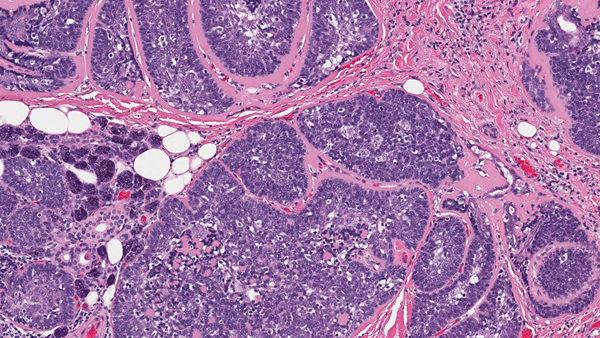

Salivary Gland Cancers

These are a rare group of cancers. They represent less than 5% of all head and neck malignancies and can also present in other areas of the body, including the windpipe, breast, skin and the vulva. Surgery, where possible, followed by radiotherapy is the most common treatment. Supporting research and clinical trials is vital to improve survival and reduce side effects in all patients.